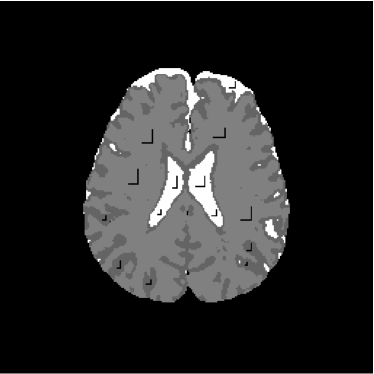

Figure 28 shows 13th slice of classification result obtained by the use of the objective dialectical classifier. Figure 29 exhibits 13th slice of classification result after performing post-labeling, whilst figure 30 shows the entire volume generated by ODC classification.

The training process of ODC algorithm resulted in 6 classes. These classes were reduced to 4 after manual post-labeling, merging 3 classes out of brain region, namely image background, noise and cranial box. The post-labeling is manual because all 3 cited regions are statistically different and, consequently, they are merged due to our interest in classes more related to the brain regions. On figure 29 it is possible to notice that ODC was able to distinguish white matter from the gray matter present in the interface between liquor and white matter.

Figure 29: 13th slice of objective dialectical classification after post-labeling